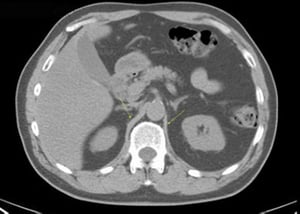

CT-Scan von Abdomen und Becken mit normaler Anatomie ohne Kontrastmittel (Folie 10)

Dieses Bild zeigt die Crura des Zwerchfells (Pfeile).

© Springer Science+Business Media